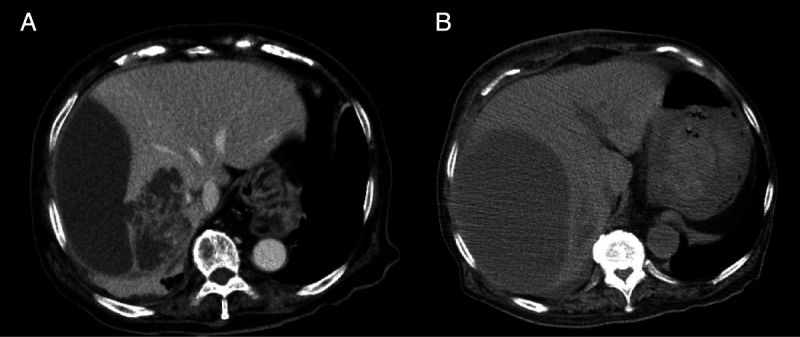

EUS-guided abscess drainage in an elderly patient with an abscess in the right liver lobe (with video).

一名右肝叶脓肿的老年患者在 EUS 引导下进行脓肿引流(附视频)。